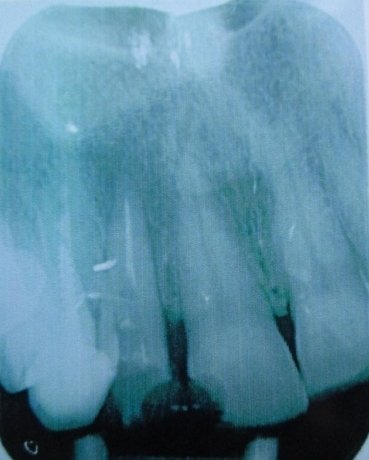

Здравствуйте! Подскажите пожалуйста, очень болит зуб вторую неделю! Нахожусь временно не в своём городе, тут гинеколог и стоматолог в одном лице. Скоро домой, договорился со своим лечащим врачом, примет по приезду 28/02, но боюсь не доживу, каждый день всё больнее и больнее. Предложили вырвать его, но он не шатается, стот крепко без кариеса вылеченный. Жевательный зуб 7, под десной сначала был красным, теперь весь зуб странного, бледного цвета. Ноет сильно пью обезболивающее. Есть снимок. Помогите пожалуйста.